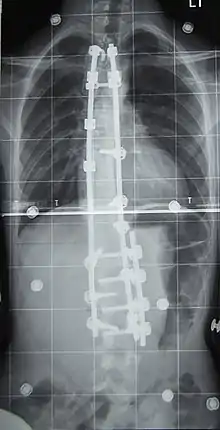

Chirurgie

L'indication concerne environ 10 % des scolioses idiopathiques du sujet jeune[2] et concerne les scolioses importantes, avec un angle de Cobb dépassant les 50°. La technique consiste en la mise en place de deux longues tiges métalliques vissées dans les vertèbres, permettant le redressement de la colonne vertébrale, notamment avec la technique et le matériel de 3e génération proposés par Cotrel et Dubousset[45]. Les complications sont essentiellement locales mais il peut exister des étirements ou compressions de racines nerveuses dans moins d'un pour cent des interventions[46].

À l'issue de l'intervention (qui peut dans certains cas corriger totalement la scoliose), le rachis est bloqué de manière définitive. Les vertèbres libres de greffe devant travailler davantage pour « compenser » l'immobilisation du reste de la colonne, des douleurs dans le dos peuvent apparaître de façon imprévisible et à tout âge. Le rachis étant un flexible conçu pour bouger - et non être bloqué, on considère que l'opération ne règle pas entièrement le problème : on supprime un défaut (la courbure) pour en créer un nouveau : la rigidité du dos liée à l'opération.